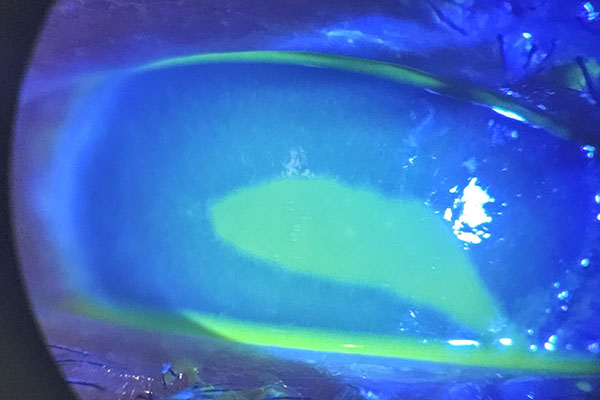

Comparison of three measurement methods of intraocular pressure in patients with keratoconus undergoing MyoRing implantation

Naderi M., Jadidi K., Mosavi S., A., Mohammadi A., H., Farahani M., Karimi F.